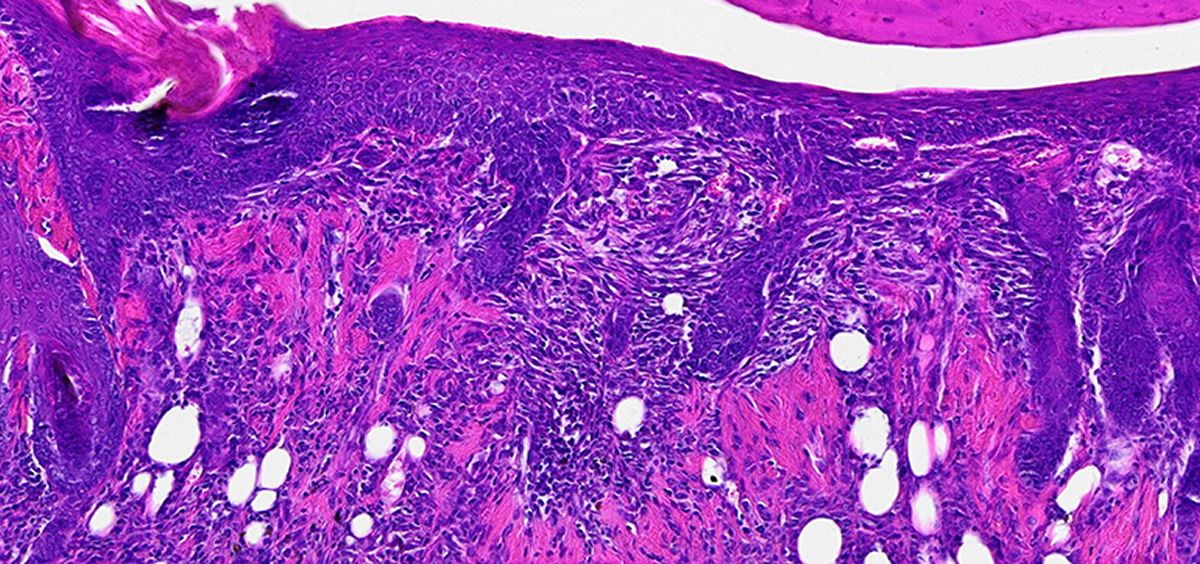

El equipo probó sus apósitos bioabsorbibles en ratas, cerdos y conejos con lesiones hepáticas, y comprobaron que su nuevo material puede detener la pérdida de sangre. Además, después de aproximadamente una semana, no quedaron señales de los apósitos dentro de los hígados de los animales.